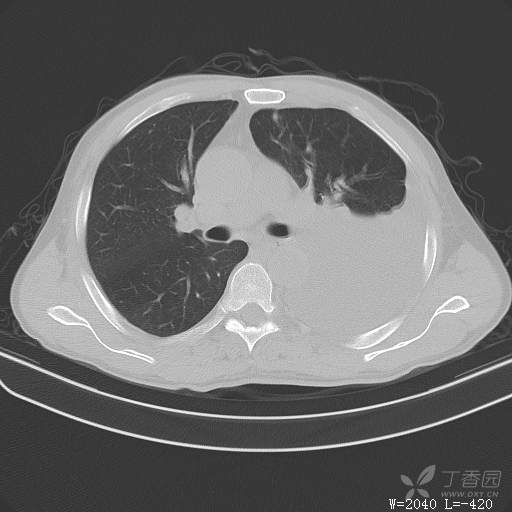

这个胸腔积液原因不寻常,大家猜猜看(得细心,这个很有意思)(俱乐部3)

简要病史:胸闷、憋气伴低热1月

体格检查:T:37.6℃;P:92次/分;R:20次/分;Bp:100/60mmHg,神清,呼吸平稳,周身未触及肿大淋巴结,右肺及左上肺叩诊清音,左下肺叩诊浊音,右肺及左上肺呼吸音粗,左下肺未闻及呼吸音,心率92次/分,律齐,无杂音。腹部平坦,软,全腹无压痛,无反跳痛及肌紧张,肝脾肋下未触及,双下肢无水肿。

临床诊断:左侧胸腔积液